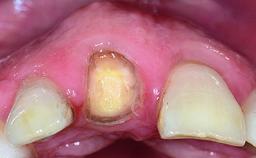

Replacement of a Missing Upper Left Central Incisor: Late Placement of an RC Bone Level Implant, CAD/CAM Zirconia Abutment

A healthy 37-year-old female patient was referred for a consultation on the replacement of missing tooth 21 with an implant-supported restoration. She stated that several years previously the tooth had been traumatically avulsed following a motor vehicle accident. The tooth was replaced with a three-unit fixed partial denture (FPD) immediately afterwards. Over time, she became disillusioned with the FPD and looked for a different option, including orthodontic therapy. She presented still in her orthodontic appliances, with the pontic sectioned free from the FPD but attached to the archwire. Her orthodontist felt that orthodontic treatment had been successfully completed, but nevertheless referred her before removing the appliances in case adjustments were necessary.